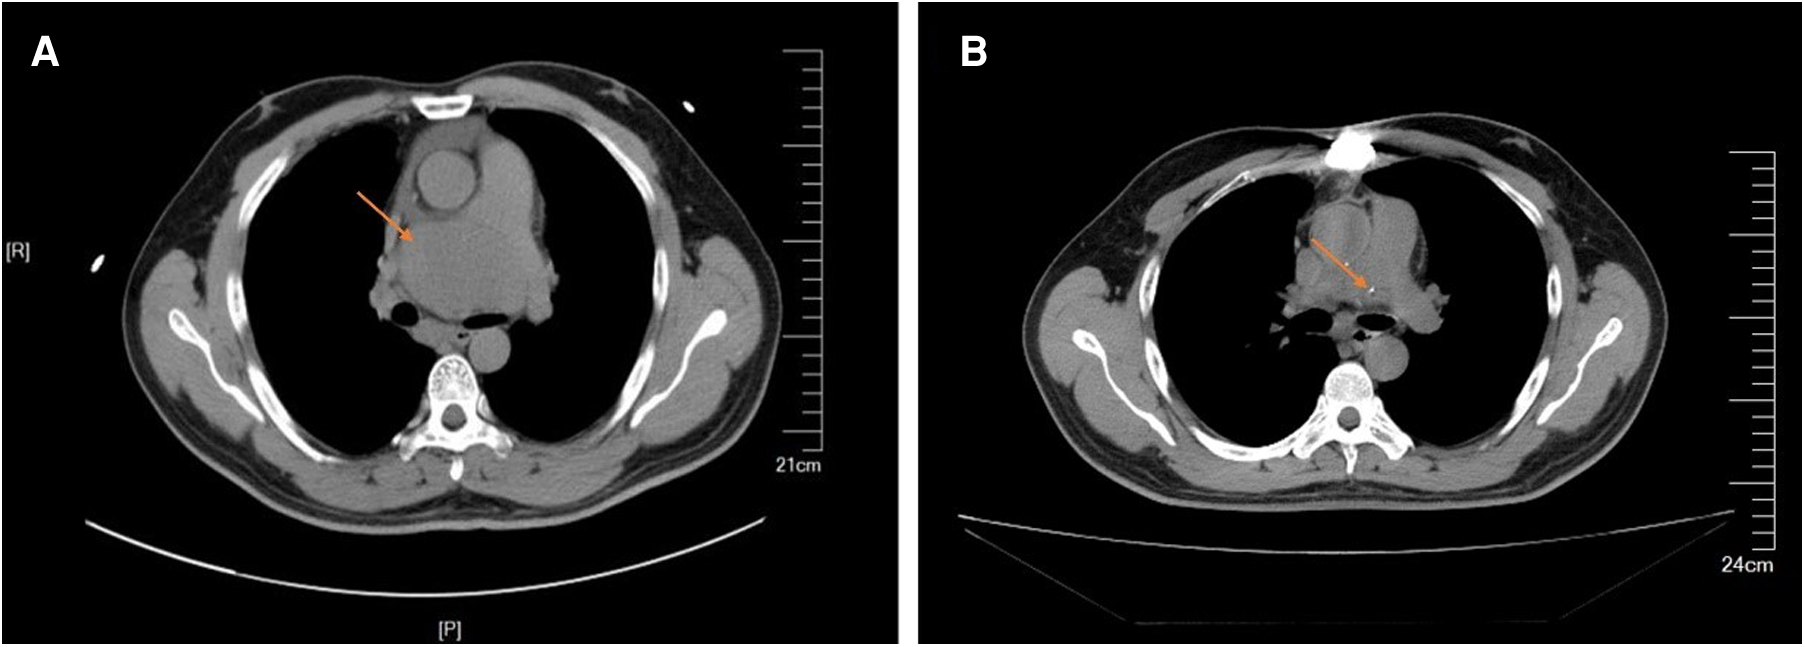

A 38-year-old man with no obvious symptoms was found to have a mediastinal tumor during a physical examination. The patient had no significant medical history except having diabetes mellitus for a year. He was referred to our hospital for medical treatment. No pathologic signs were found through other physical examinations. His laboratory test results were all within the normal limits, except for the lymphocyte count (13.1%), which was lower than the normal range. The levels of tumor markers alpha-fetoprotein, human chorionic gonadotropin, and lactate dehydrogenase were all normal. The thoracic computed tomography (CT) scan revealed a huge soft tissue density shadow of 72 × 48 mm in the mediastinum. The tumor was compressed near the main pulmonary artery bifurcation and extended along the right pulmonary artery and did not have clear boundaries (Figure 1). His cardiac ultrasonography revealed a huge pericardial effusion, approximately 28 mm. Considering the location of the tumor and the risk of bleeding, we did not schedule a biopsy for him. The tumor was planned for resection via median sternotomy.

Figure 1

Preparative computed tomography scan of the chest showing in the anterior mediastinum. (A) The mass close to the main pulmonary artery bifurcation and extended along the right pulmonary artery. (B) Lateral view of 3-D computerized tomography showing the mass between aortic arch and pulmonary artery.